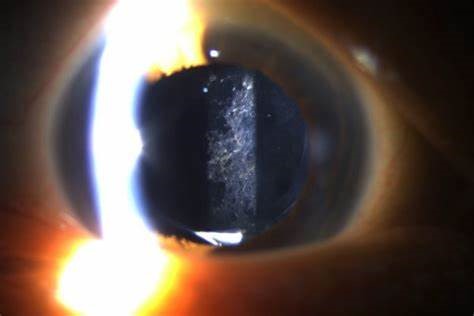

Our courses for ophthalmologists will develop your skills across the full range of eye conditions, whilst providing the latest thinking in ophthalmic health from world leading experts.